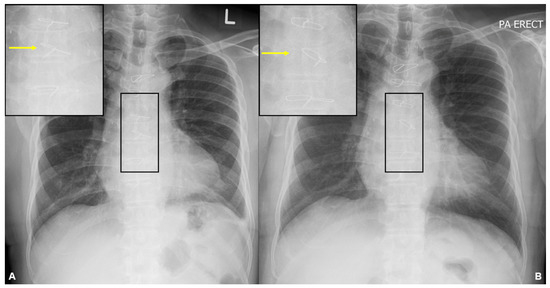

A subsequent 18-fluorodeoxyglucose (FDG) whole-body positron emission tomography-computed tomography (PET-CT) study (A) shows intense FDG avidity at multiple sites, including the index sternal lesion (SUVmax 4.9) [indicated by the dotted red arrow] and other foci in the left frontal skull (1.5 cm, SUVmax 4.6), right humerus (4.4 cm, SUVmax 3.5), lower thoracic vertebra (2.1 cm, SUVmax 7.4), and right femur (9.5 cm, SUVmax 4.7) [indicated by solid red arrows in a cephalocaudal direction, respectively]. The patient’s multifocal osteolytic lesions, anaemia with a haemoglobin level less than 10 g/dL, and a bone marrow clonal plasma cell percentage of 60% were consistent with a diagnosis of multiple myeloma, as set out in the 2014 International Myeloma Working Group (IMWG) criterion [8]. Bone disease is present in up to 90% of multiple myeloma patients. It is related to increased osteoclastic activity, mediated by osteoclast-activating factors and local cytokines such as interleukin-6 and tumour necrosis factor-α. This can result in diffuse osteoporosis, solitary or multiple osteolytic lesions, fractures, and hypercalcemia from increased bone turnover. Imaging plays a pivotal role in the detection and assessment of the extent of bone disease. In suspected multiple myeloma, low-dose whole-body CT or FDG PET-CT is recommended to identify osteolytic lesions (>5 mm in size) [9]. Focal osseous radiotracer uptake on FDG PET-CT alone is insufficient to fulfil the IMWG criterion for bone lesions in the absence of osteolysis. If CT or PET-CT is negative or inconclusive, MRI can be a more sensitive modality in detecting focal lesions (>5 mm in size) before osteolytic bone destruction is evident [9]. Radiographic skeletal surveys are no longer recommended as a first-line investigation. In terms of staging and prognostication, the 2005 International Staging System (ISS) score considers two parameters—high serum β2-microglobulin levels reflect a high tumour burden, while low serum albumin levels are related to the presence of inflammatory cytokines such as interleukin-6 in the myeloma microenvironment. The Revised International Staging System (R-ISS) [10] incorporates two additional parameters that demonstrate impact on survival—the elevation of serum LDH level reflects a high proliferation rate, while the presence of high-risk cytogenetic abnormalities (namely, del(17p), translocation t(4;14)(p16;q32), or translocation t(14;16)(q32;q23)) are associated with aggressive biological behaviour. Patients with R-ISS stage I, II, and III have 5-year overall survival rates of 82%, 62%, and 40%, respectively [11]. Prompt treatment of active multiple myeloma is essential to prevent further complications and organ damage. The addition of autologous stem cell transplantation has been associated with longer progression-free survival [12], while novel agents such as daratumumab have also increased treatment efficacy [13]. Our patient was able to achieve response with a regimen of daratumumab, bortezomib, thalidomide, and dexamethasone (D-VTd). The precordial lump was no longer palpable after the first cycle of systemic therapy in the repeat FDG PET-CT study conducted three months after the initiation of treatment, showing a marked improvement in the previously seen lesions (B). Local radiotherapy to the index sternal lesion was not offered to the patient due to the prompt response to systemic therapy with resolution of the pain associated with the precordial lump. The other osseous lesions were also not symptomatic, negating the need for palliative radiotherapy [14]. Six months after the initial diagnosis, our patient also underwent autologous stem cell transplant which was shown to improve progression-free survival in the CASSIOPEIA trial [15].